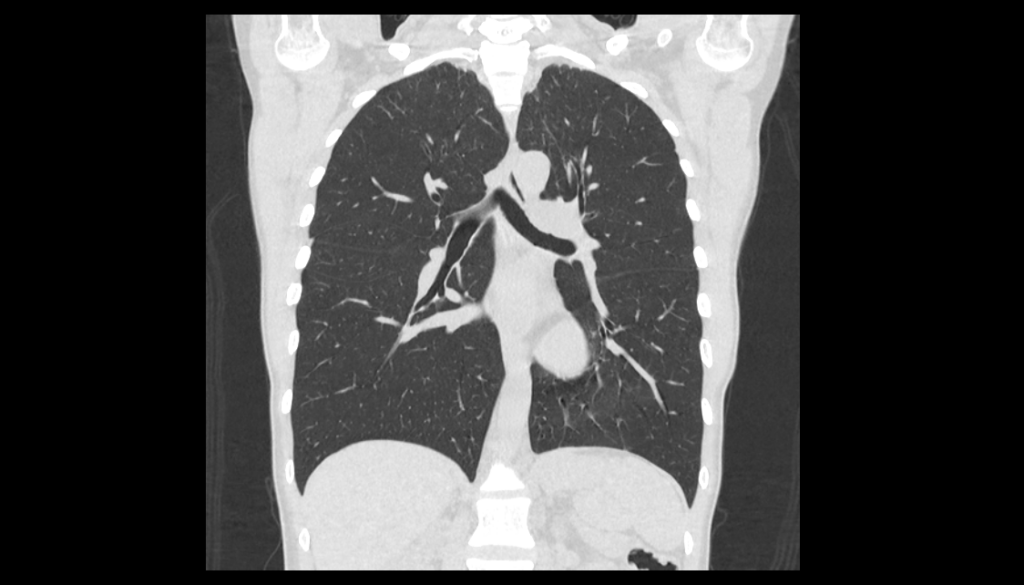

КТ

Как известно, хорошо себя зарекомендовал и попал в массы КТ во время пандемии, ассоциированной с новой коронавирусной инфекцией. Действительно, всего лишь за считанные секунды, томограф делает множество срезов, которые потом моделирует в объемное изображение и выдает на экран. Степень визуализации является достаточной, чтобы сразу же подтвердить или заподозрить ту или иную патологию. Немаловажным, является возможность проведения КТ с контрастным усилением, которое имеет высокую диагностическую ценность в поиске мельчайших злокачественных новообразований (показывает дефекты накопления, а также оценивает кровоток в сосудах, питающих легочную ткань) и патологий сосудов (мальформации, аневризмы, тромбоз сосудов и т.д.). Стоит помнить, что КТ является методом лучевой диагностики и предполагает при проведении исследования лучевую нагрузку, к которой без надобности не стоит прибегать.